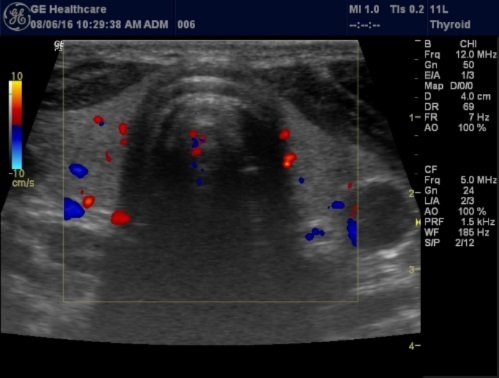

Histologically, if the excised gland has volume <500 mm3 it is said to be hyperplastic and if the volume is more than 500 mm3 it is nodular hyperplasia in 80% of cases26. In secondary HPT, the increase in the volume of parathyroid glands is associated with increase in vascularity, as evident in Color Doppler imaging 27.